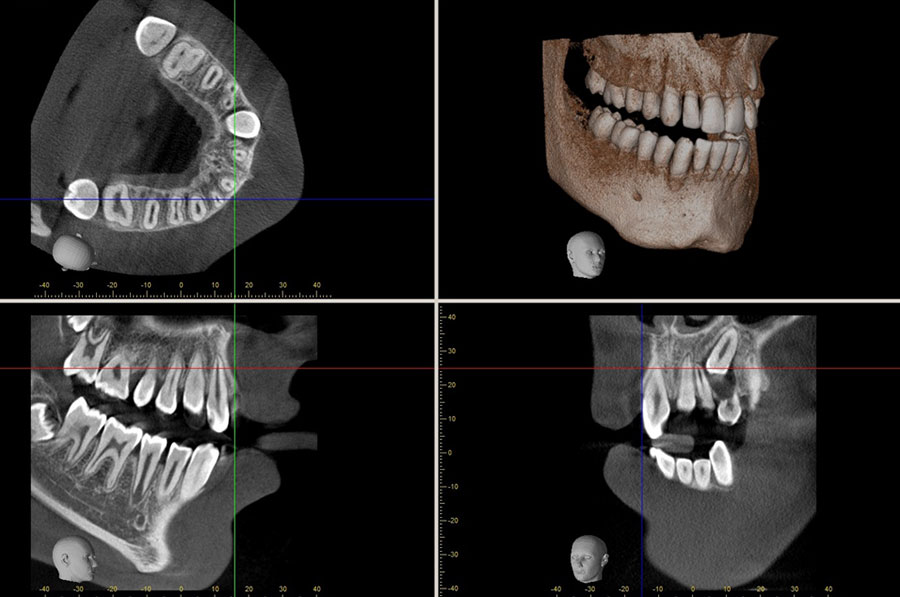

Dental tomografi X ışını kullanmak suretiyle ilgi alanı dışındaki görüntülerin odak dışında bırakılarak istenilen bölgedeki objelerin daha net bir şekilde görülmesini sağlayan, ince kesitlerden oluşan ve hacim içeren görüntü elde etmeye yardımcı olan bir yöntemdir. Klasik diş röntgeni ile arasındaki ana fark, bir volumetrik tomografinin bize 3D görüntü verebilmesidir. Bu da uzunluk, genişlik ve derinlik de dahil üç boyutlu görüntüleme ve tüm dişlerin, çene kemiğinin ve hatta hava yolunun etrafını görebilmemiz anlamına gelir!

Dental konik ışın bilgisayarlı tomografi (CBCT) teknolojisi, diş hekimlerinin hastalarını daha etkili bir şekilde tedavi etmelerine olanak tanıyarak diş radyografik görüntülemenin sonuçlarını kökten değiştirmiştir. Bu teknoloji, diş hekimlerinin saf tanıyı daha doğru yapmalarını sağladığı gibi, hekimlerin tanı ile yetinmeyip daha ileri bir aşamaya geçerek tedavi simülasyonlarını planlamasına izin vermiştir.

CBCT görüntüleme, kapsamlı verileri ve anatomiyi birçok açıdan inceleyerek bu verileri dinamik olarak manipüle etme yeteneği sunar. Ortodontik olguların, solunum yollarının, etkilenen dişlerin ve periodontal defektlerin değerlendirilmesi ile birlikte TME durumu ve düzensizliği veya çene patolojisinin teşhisi, CBCT görüntülemesi kullanılarak kolaylaştırılmıştır.

Üç boyutlu tomografiler ile maksillofasiyal anatominin çoğunu görüntülemek mümkündür. Daha geniş görüş alanlı CBCT genellikle çene cerrahisi ve ortognatik cerrahi uzmanlık pratiğinde uygun olanıdır, daha küçük görüş alanlı CBCT’ ler ise implant planlamadan, çatlak tespitine, endodontiden, lezyon görüntülemeye kadar her türlü detaylı tanı gerektiren tedavide kullanılabilir.

CBCT görüntüleme, üretilen görüntülerin yüksek kalitesi, yazılım özellikleri ve düşük radyasyon maruziyet dozları nedeniyle implantoloji için ideal radyolojik yöntemdir. CBCT ve implantoloji ile ilgili en önemli konulardan ikisi sanal cerrahi planlama ve cerrahi kılavuzlardır. Diş hekimlerinin kemiğin yoğunluğunu gölgeleme yoluyla değerlendirmesini sağlayan özel yazılım uygulamaları ile sanal bir ameliyat yapılabilir ve 1: 1 ölçüm aletiyle kemiğin boyutları doğru bir şekilde kaydedilebilir. Çene sınırları, bitişik dişler, nazal fossa, mandibular kanal, maksiller sinüs, mental foramen ve insizive kanal dahil implant yerleşimini değerlendirmek için gereken ortak iç anatomi tanımlanabilir. Ayrıca implant sağlığı için kaçınılması gereken patolojiyi de tespit eder. Bu nedenle, ameliyattan önce, klinisyen uygun implant boyutunu doğrulayabilir.